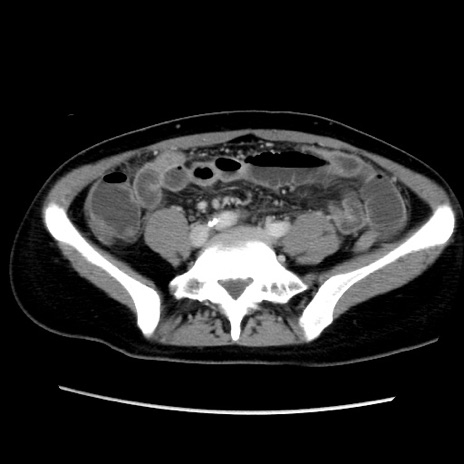

症例39(横断像)

【症例】40歳代女性

【主訴】上下腹部痛

【現病歴】2日目から下腹部痛あり。夜間は痛みで眠れなかった。昨日より上腹部痛と下痢が出現。臥位で痛みは軽快したため、休んでいた。本日になって臥位でも立位でも痛みが強くなってきたため救急要請。

【既往歴】子宮内膜症

【身体所見】部:平坦・軟、左上下腹部に圧痛あり、反跳痛あり。

【データ】WBC 21800、CRP 26.78